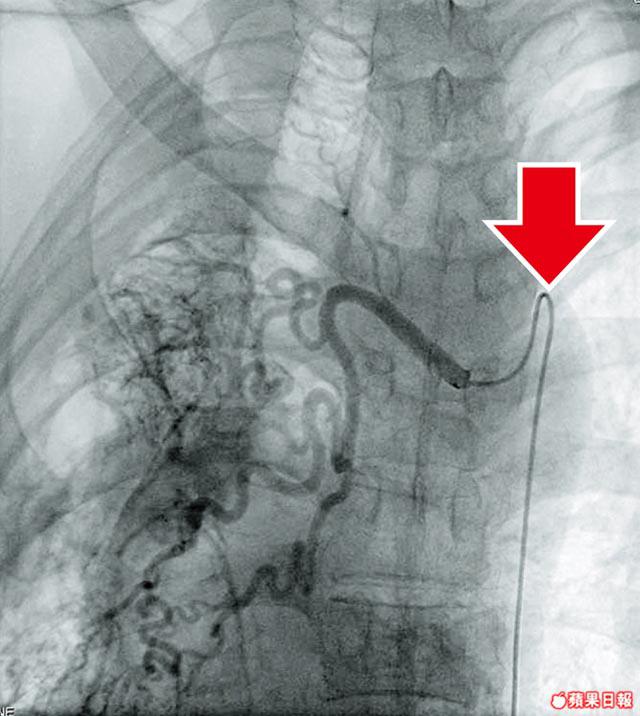

聯合醫院放射及器官造影科副顧問醫生陸永恒表示,聯合醫院99至2000年間引進支氣管動脈栓塞術,以治療大量咳血。方法是先為病人進行氣管動脈造影,找出不正常的動脈,再將小導管放入病人的腹股溝動脈,經腹部及胸部大動脈,到達不正常的支氣管動脈。然後透過小導管引入有止血功能的微粒,堵塞出血血管。

陸表示,聯合醫院每年平均為15名病人做支氣管動脈栓塞術,一般手術只需半小時,但曾有病人6條動脈出血,手術長達6小時。